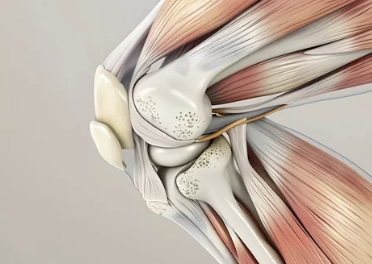

무릎 연골은 뼈와 뼈 사이에서 완충 작용을 하여 관절의 부드러운 움직임을 돕고, 마찰을 줄여주는 역할을 해요.

- 연골의 종류: 무릎에는 반월상 연골과 관절 연골, 두 가지 종류의 연골이 있어요. 반월상 연골은 무릎 안쪽과 바깥쪽에 C자 모양으로 위치하며, 충격 흡수와 안정성 유지에 중요한 역할을 합니다. 관절 연골은 뼈 끝 부분을 덮고 있으며, 뼈끼리 부딪히는 것을 막아주고 부드러운 움직임을 가능하게 해요.